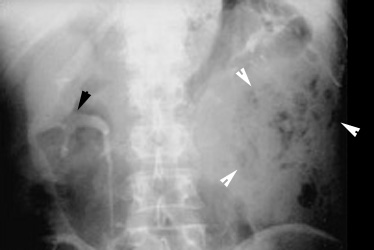

Renal abscess

CT shows a large mass in the left renal area with multiple air pockets and absence of functioning renal parenchyma. |